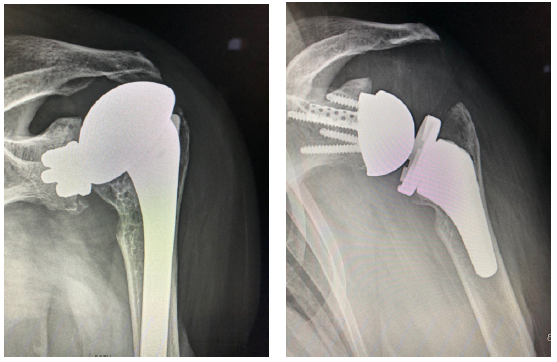

Patient 3: Revision of a failed anatomic total shoulder with loose humeral stem to reverse total shoulder arthroplasty

- The humeral stem was loose, so it was replaced with the short stem for the aggressive proximal geometry, which fit nicely and improved the proximal press-fit

- Revised an anatomic to a reverse, replacing stem from another company

- Significant glenoid wear led to augmented baseplate choice – superior posterior augment

Patient 3: 74-year-old female with cuff tear arthropathy.

- Right primary reverse shoulder arthroplasty with augmented baseplate to treat glenoid wear.